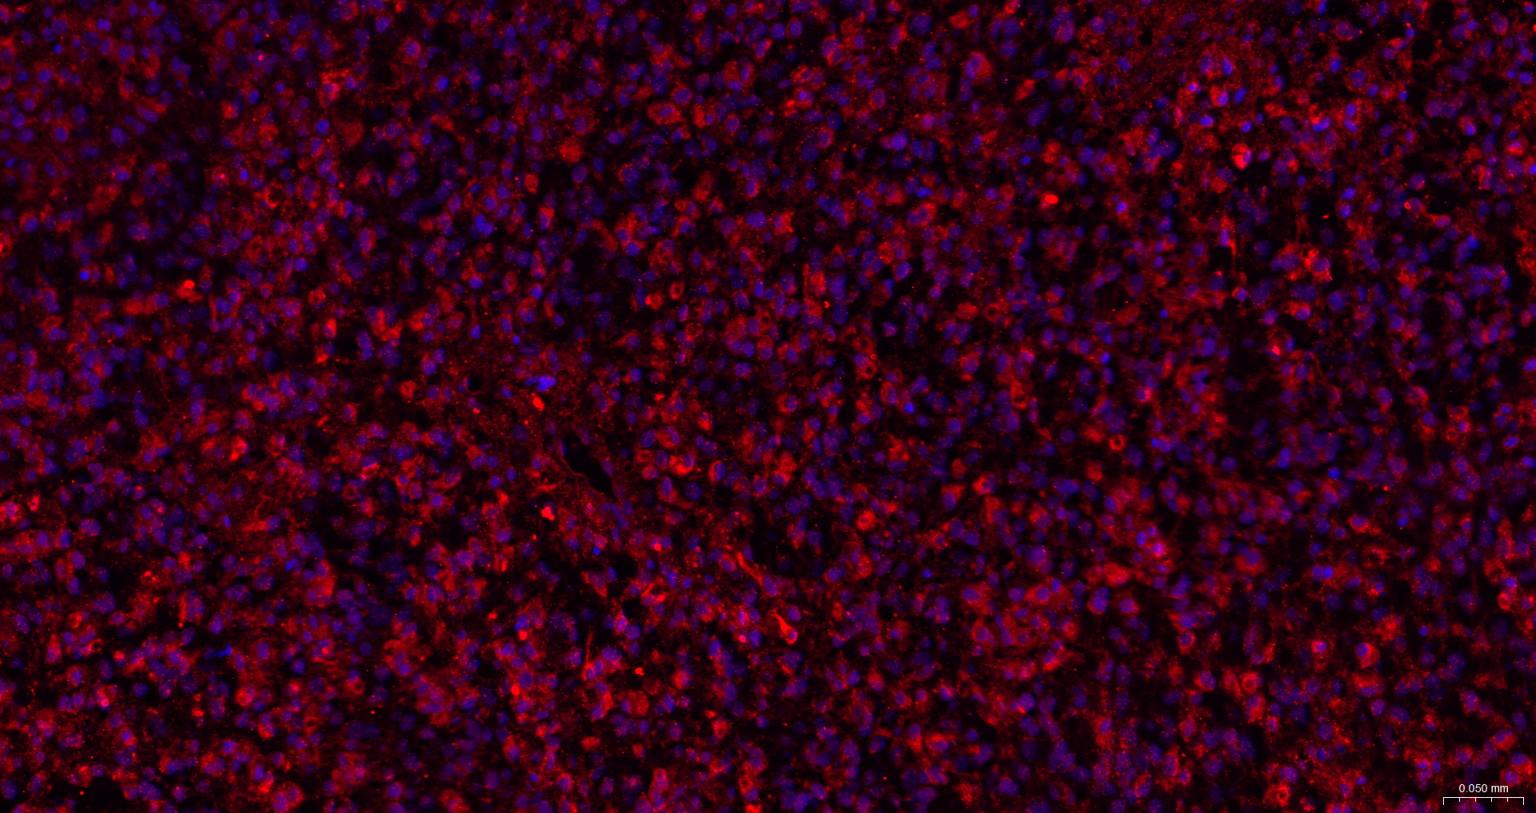

Paraformaldehyde-fixed, paraffin embedded Human Glioblastoma; Antigen retrieval by boiling in sodium citrate buffer (pH6.0) for 15 min; The section was incubated with IRE1 Polyclonal Antibody, Unconjugated (bs-8680R) at 1:200 overnight at 4°C. Followed by conjugated Goat Anti-Rabbit IgG antibody (Red, bs-0295G-BF594), DAPI (blue, C02-04002) was used to stain the cell nuclei.